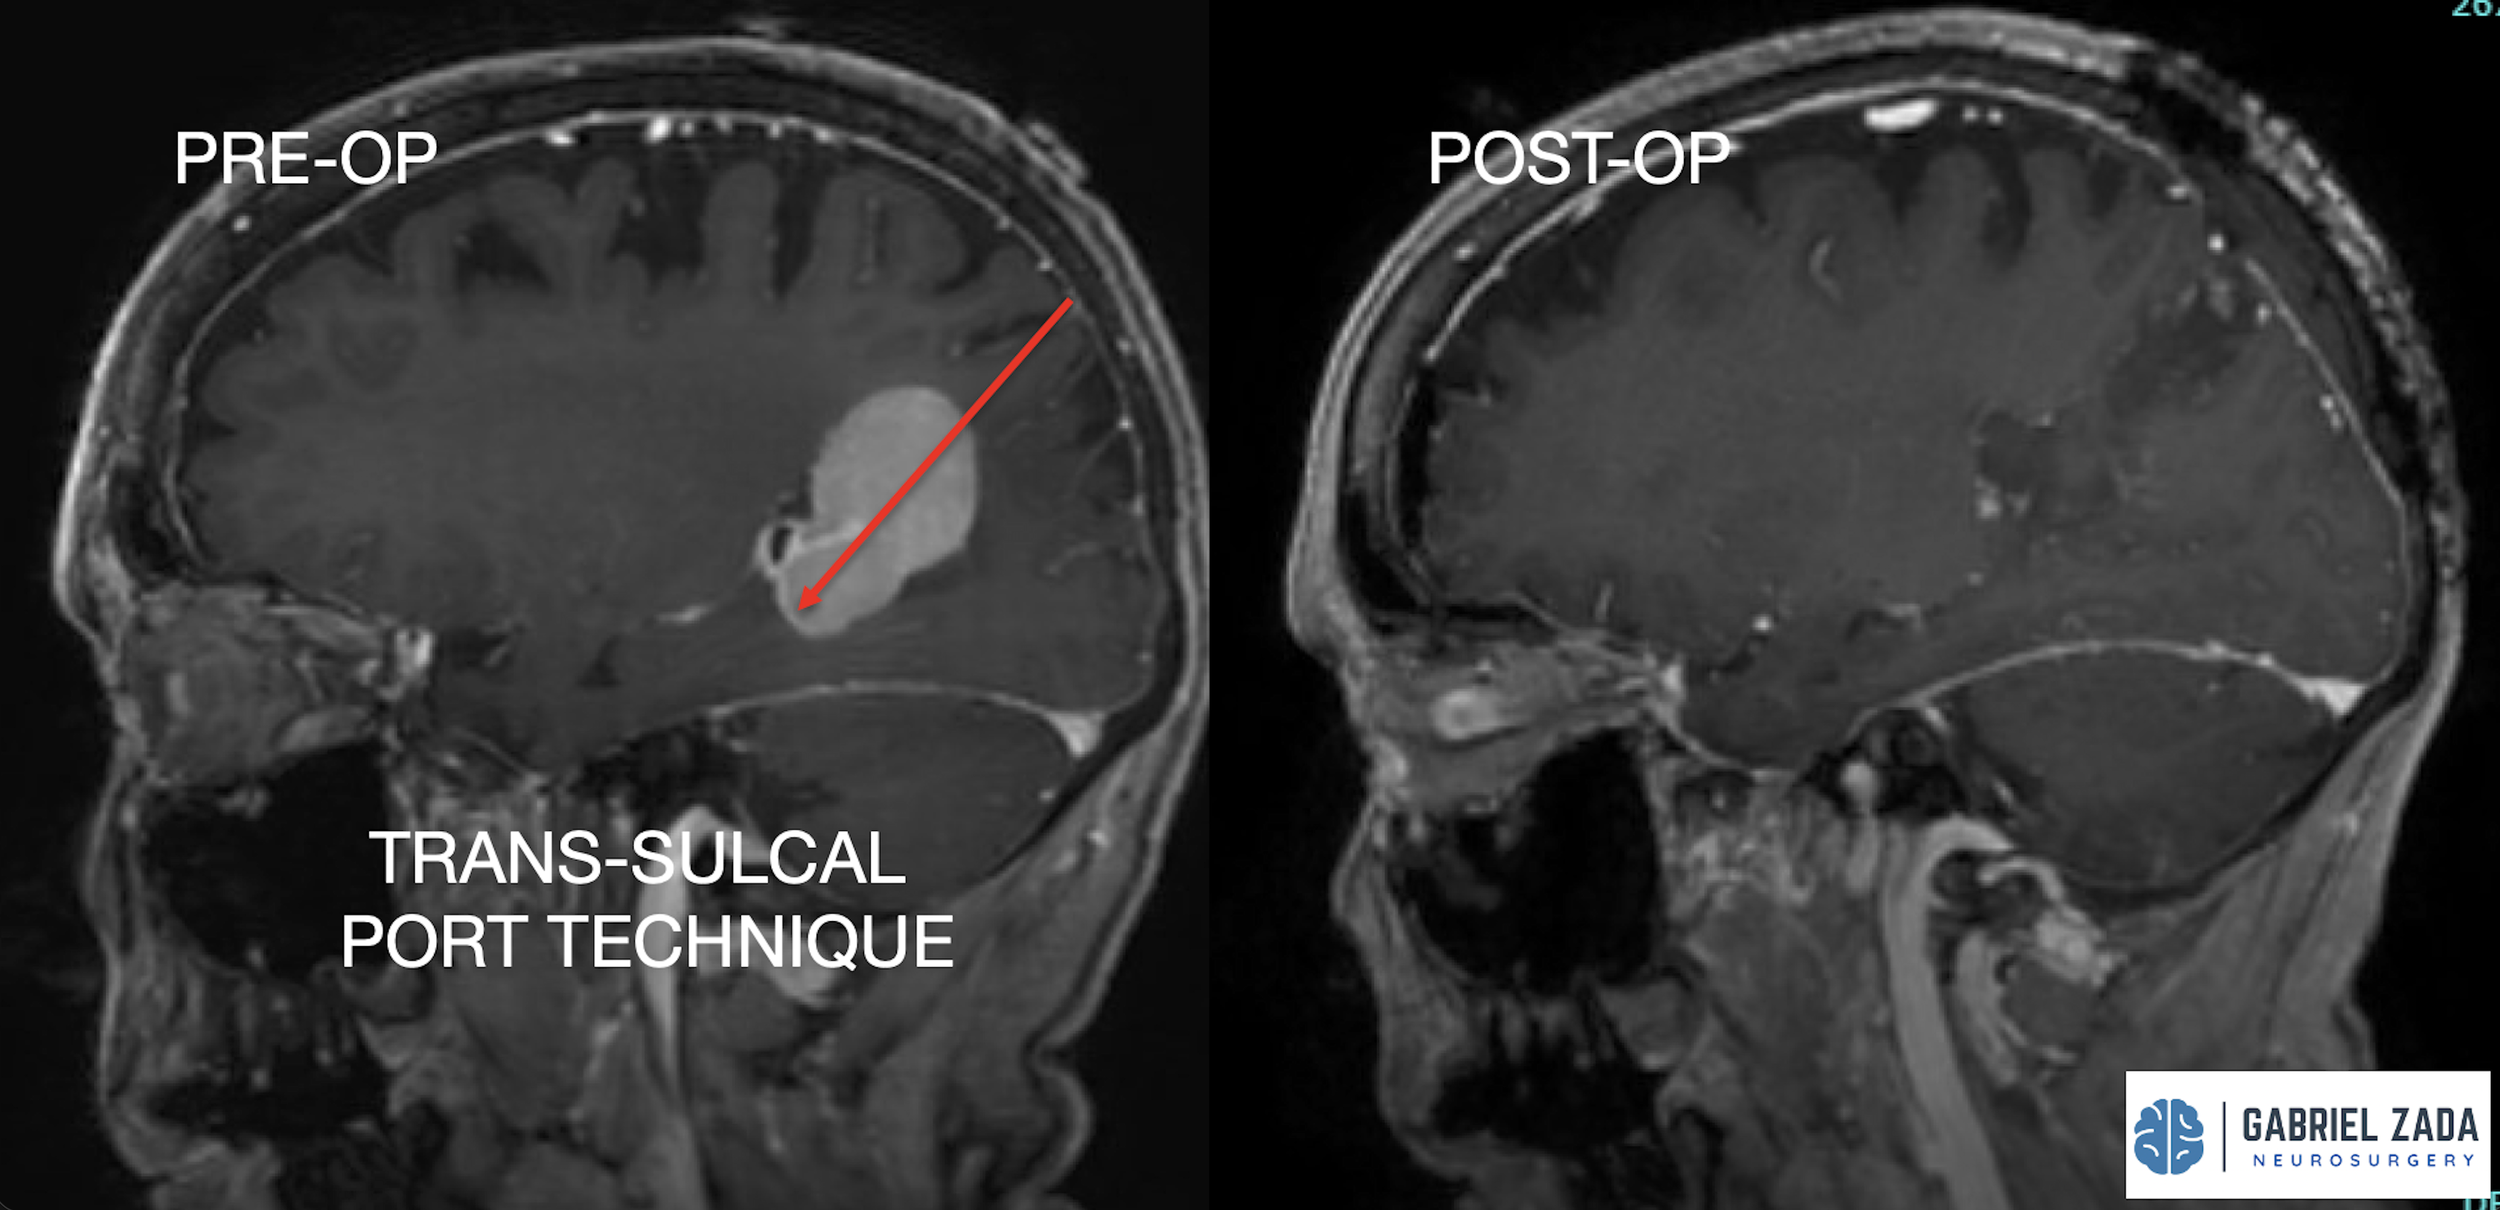

Explore this comprehensive gallery featuring pre‑ and post‑operative imaging of patients with skull‑base tumors treated by Gabriel Zada, MD, MS, FAANS, FACS. These cases highlight Dr. Zada’s expertise in advanced neurosurgical techniques and outcomes.

*Representative cases shown for educational purposes. All images de-identified. Individual results vary.